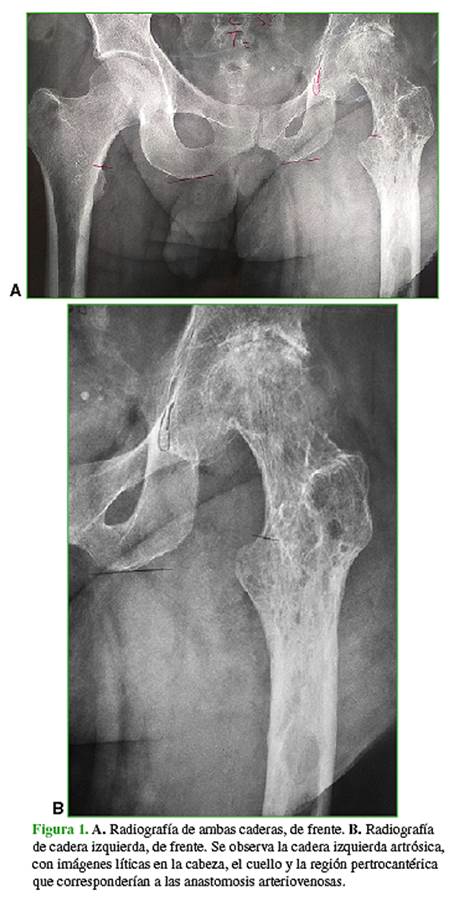

Paciente de 54 años con diagnóstico de síndrome de Klippel-Trenaunay que afecta el miembro inferior izquierdo y artrosis de la cadera homolateral de cinco años de evolución (Figura 1). El miembro inferior izquierdo tiene un diámetro mayor que el contralateral, y se detectan múltiples cordones varicosos con latido palpable en la ingle, el tobillo y la región glútea posterior (Figura 2). El paciente camina con bastón y la cadera en flexión y hay acortamiento del miembro. Presenta escoliosis lumbar y lumbalgia; la rodilla homolateral no está afectada.

Se realizó una resonancia magnética en la que se constató la alteración de la arquitectura ósea por malformaciones vasculares en la cabeza, el cuello y la metáfisis femoral (Figura 3).

Se programó la colocación de una prótesis total de cadera híbrida, cotilo no cementado y tallo cementado, considerando la arquitectura del fémur proximal (Figura 1) y que, en la resonancia magnética (Figura 3), se observaban múltiples imágenes intraóseas correspondientes a fístulas arteriovenosas. La idea era disminuir el sangrado intracanal con el cementado.

Analizando las radiografías de cadera de los casos publicados, en los tres pacientes en quienes se completó el reemplazo articular, la alteración intraósea no era tan significativa, como en la que debió suspenderse el procedimiento y en el nuestro (Figura 1).